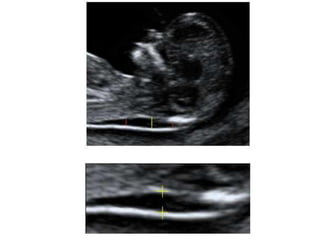

TRANSLUCENCIA NUCAL

• Personal entrenado, Ecógrafo de alta resolución

• Transabdominal, LCC:45-84mm

• Corte sagital medio. Feto en posición neutra.

• Incluyendo en la imagen sólo cabeza y tórax.

• Magnificación de la imagen(75%).

• Calipers emplazados de interno- interno de los bordes de la

TN y en sentido perpendicular.

• Diferenciar el amnios de la piel

TRANSLUCENCIA NUCAL • Personalentrenado, Ecógrafo de alta resolución • Transabdominal, LCC:45-84mm • Corte sagital medio. Feto en posición neutra. • Incluyendo en la imagen sólo cabeza y tórax. • Magnificación de la imagen(75%). • Calipers emplazados de interno- interno de los bordes de la TN y en sentido perpendicular. • Diferenciar el amnios de la piel